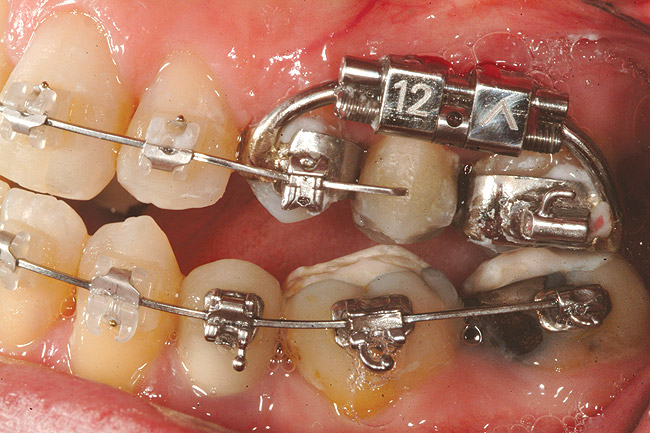

Fig 12 (and Fig 13). Incisors were too upright and had severe incisal wear. He was concerned about esthetics of the worn teeth and his insufficient lip support. Progress photo and panorex 9 months after corticotomies were performed on Nos. 6 through 11. Previous extraction sites were reopened orthodontically to improve function and fill lip support. Incisal edges were restored provisionally with composite resin. Note that despite the creation of adequate spaces to replace missing teeth, there is inadequate room for placement of dental implants because of severe tipping of all the anterior teeth. Osteotomy SFOT may have been a better choice because it would have allowed needed alveoloskeletal correction (without excessive tipping) instead of the primarily dentoalveolar correction common in corticotomy SFOT. Restorative dentist: Brad Jones, DDS.

Figure 12

Fig 13 (and Fig 12). Incisors were too upright and had severe incisal wear. He was concerned about esthetics of the worn teeth and his insufficient lip support. Progress photo and panorex 9 months after corticotomies were performed on Nos. 6 through 11.

Figure 13